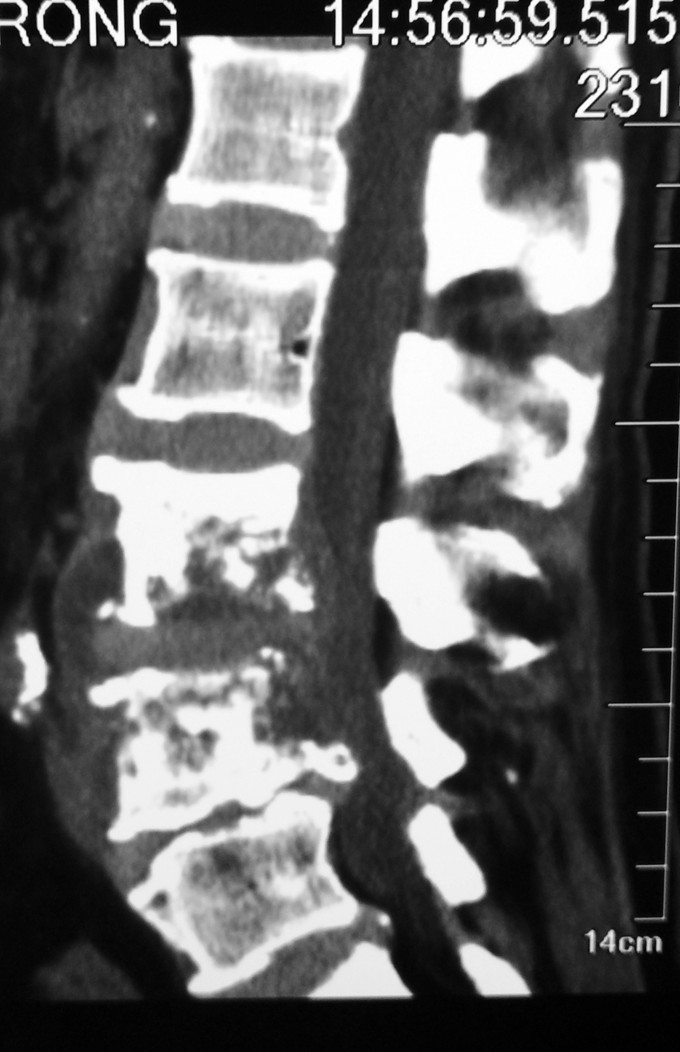

1.腰3-4结核 2.腰4-5椎管狭窄 因术前血沉比较高,所以予以HREZS抗痨治疗2周,血沉至44mm/h,患者一般情况较前好转。安排手术治疗:后路腰3-4椎间病灶清除椎板植骨+腰4-5减压植骨内固定融合术。

此患者腰椎结核伴有相邻节段椎管狭窄,所以兼有两者的症状。对于此病例我们考虑因患者椎体前方脓肿不明显,所以考虑一起行后方椎间隙病灶清除,植入自体椎板骨融合内固定,同时进行腰4-5后路减压内固定融合术。 不知大家对结核的病人一般是通过何种方式进行病灶清除的?选择原则是什么?